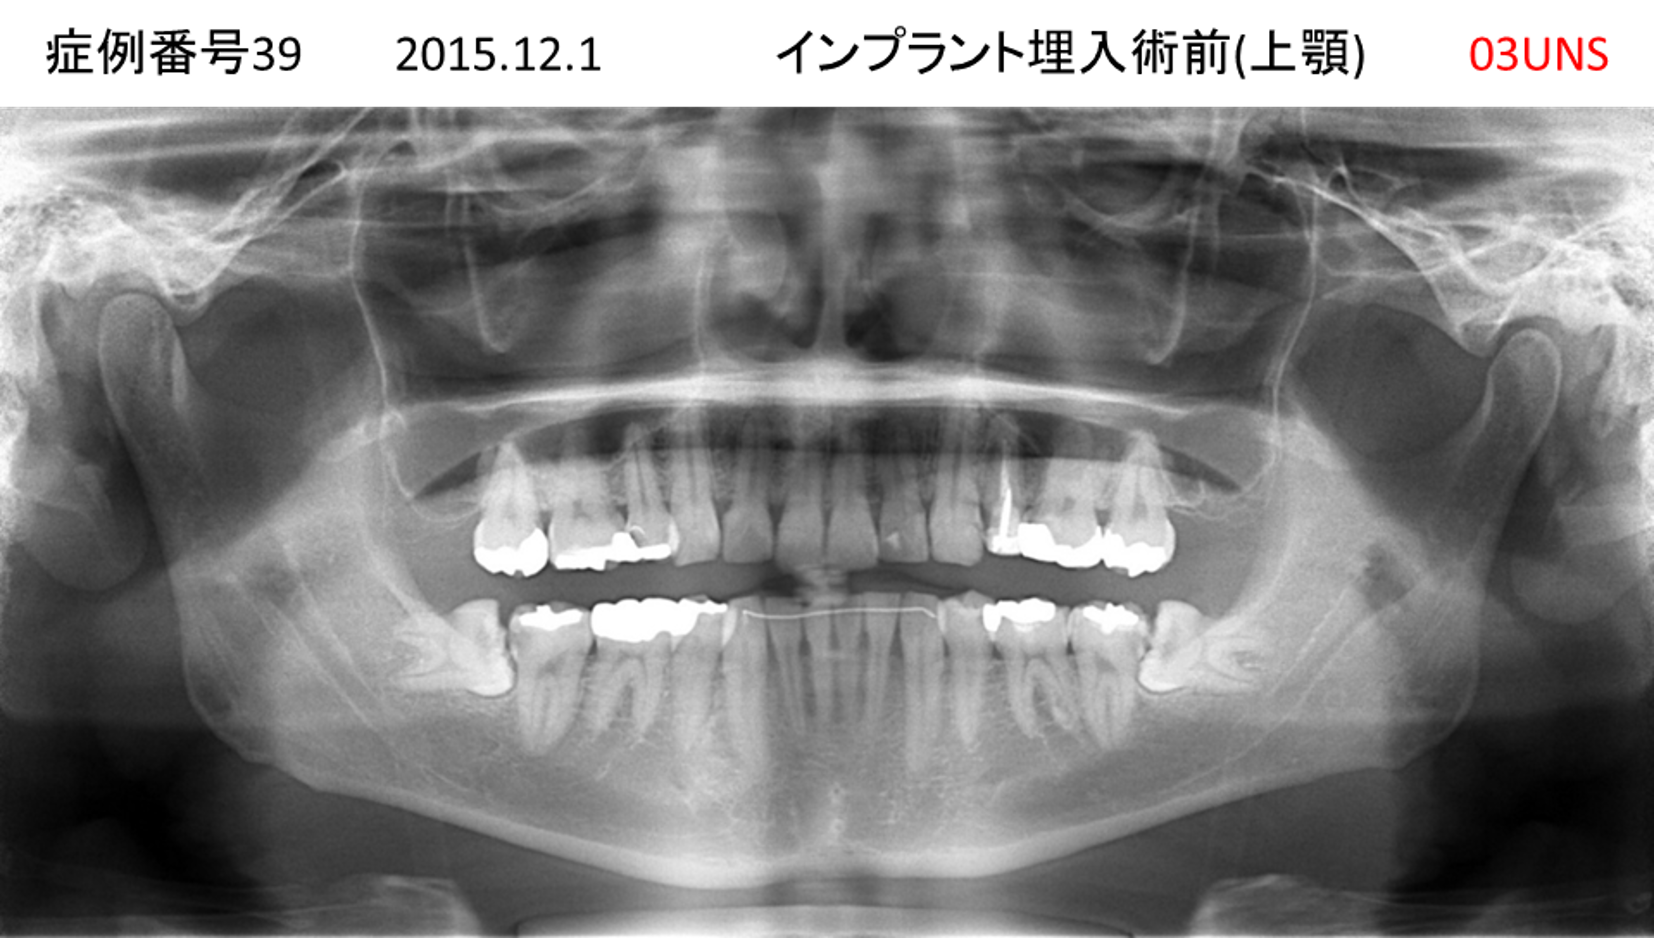

義歯が合わない、噛めない患者様のインプラント症例

| 治療名称 |

インプラントコーヌステレスコープ |

| 治療費用 |

270万円+税 |

| 治療期間 |

4か月 |

| 患者さんの症状(主訴) |

義歯が合わない、噛めない |

| 治療内容 |

インプラント、義歯作製(コーヌステレスコープ) |

| 治療結果 |

しっかり噛めるようになった。見栄えが良くなった。 |

| 治療の注意点(リスク/副作用) |

義歯が壊れた場合、インプラントが壊れた場合は再治療が必要 |